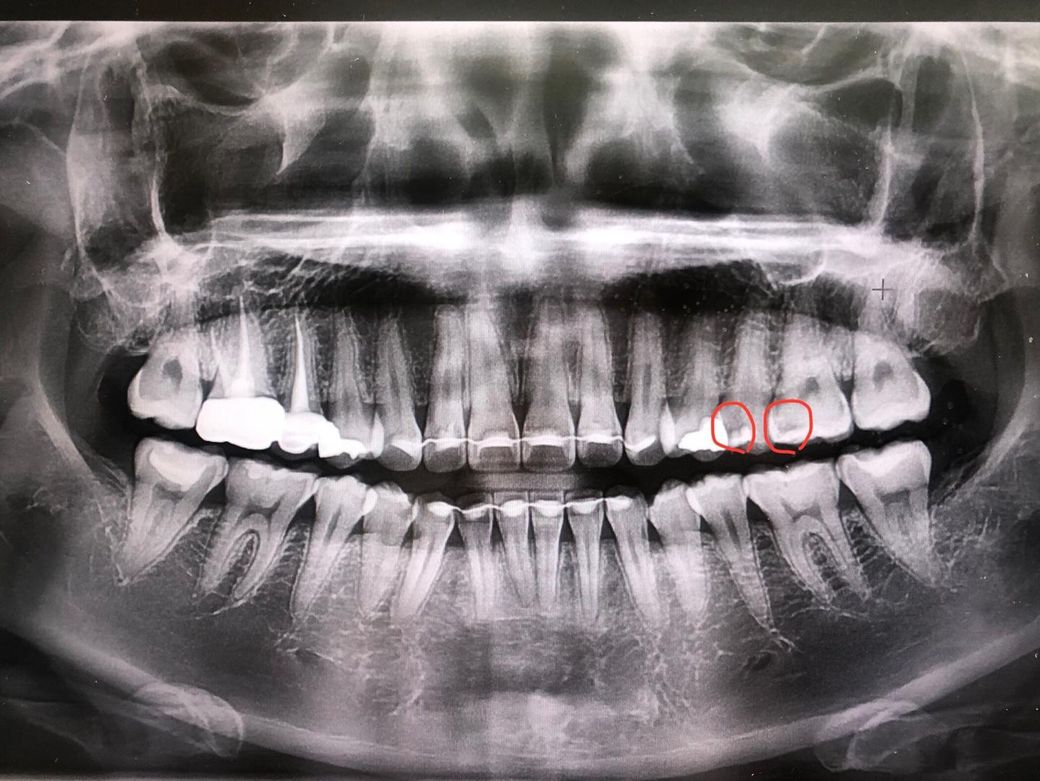

치아 치료(크라운) 가격대는 얼마쯤할까요

치과병원마다 가격대가 다른거같아요.

크라운쒸운다고하면 대략 얼마정도 나올까요

가격대가 높지않은걸로요;;

골드/메탈/치아색 <---평균 대략 가격이 궁금합니다

골드는 요즘 가격이 많이 올라서 최소 70만원 이상 지르코니아는 보통 5-60만원 정도 합니다.

평균 가격을 말씀드리자면 골드 50~60, 지르코니아 60, 메탈 30 정도라고 보시면 됩니다